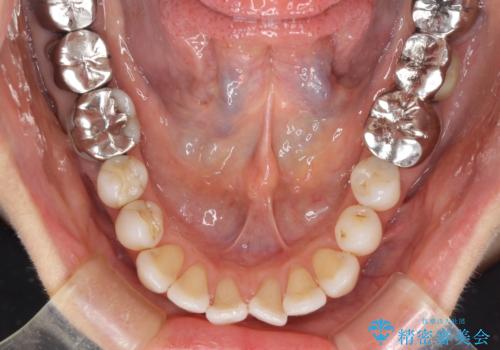

- 前歯の上下スペースと前歯の隙間を気にして来院された患者様です。

インビザラインにより上下の前歯の隙間を閉じながら、IPRを用いて口元の突出感を合わせて改善していくこととしました。

上下の隙間に舌が入り込むことが、すきっ歯やオープンバイトの原因であったため、舌の筋肉のトレーニングも並行して行い、後戻りの抑制を図りました。